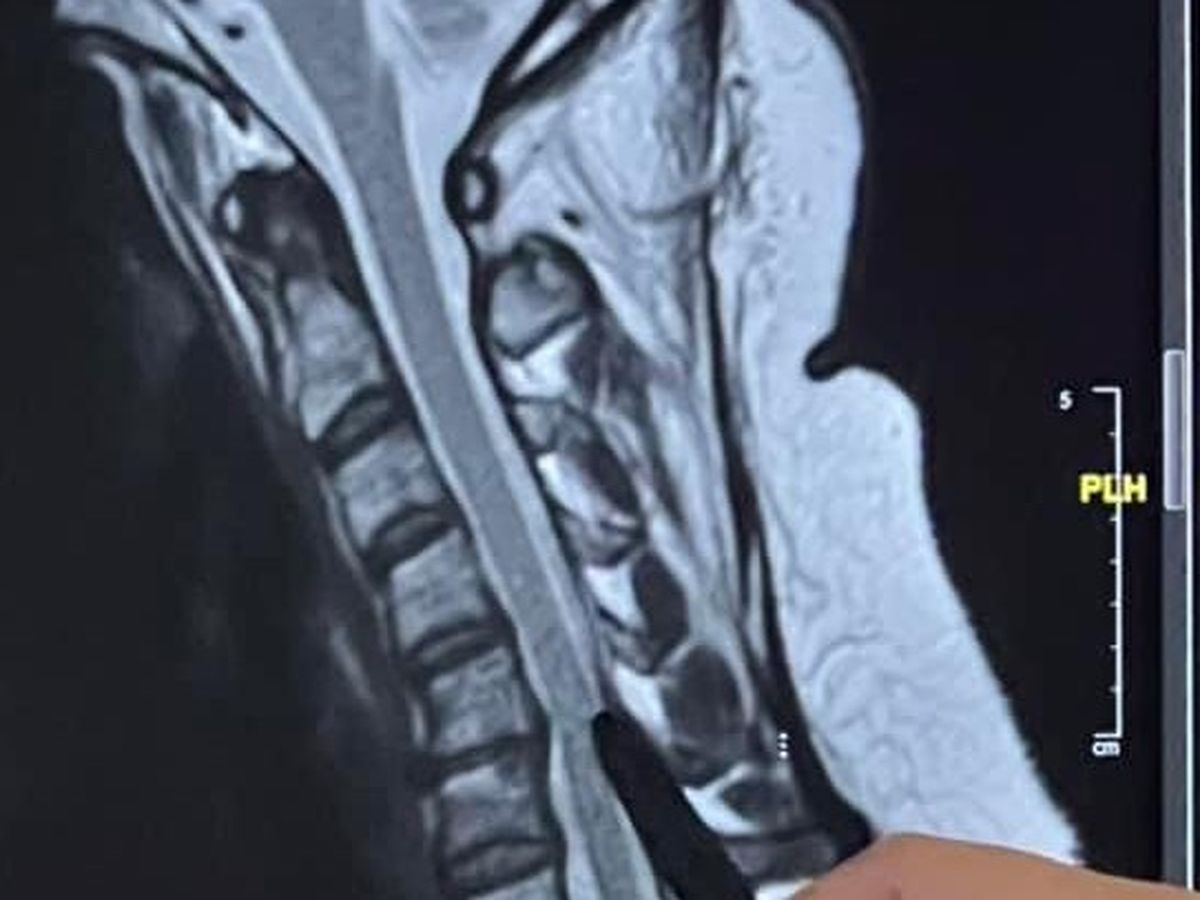

”I am still in hospital and have been since Monday. When I collapsed at work, I incurred a very serious injury to my neck. The vertebrae is touching my spinal cord and I need extensive surgery. It’s very dangerous and involves a lot of preparation and planning. I have been put on strong anti-seizure medication and steroids. I am being monitored by both cardiologists and neurologists. The head neurosurgeon is putting together multipart plan to treat in the safest and most effective way so I have the greatest chance for living a long successful life without loss of permanent mobility. I have been haltered with a heart monitor. I am in a very scary situation and my kids are beyond scared. I will know a lot more hopefully tomorrow and days to follow. The medications are very difficult and effect my mood dramatically. I’m unable to drive. My left side of my body is numb. I have decreased motor skills and my balance is off and I am wobbly. Hoping to discharge from hospital and meet individually with specialists to devise a plan to successfully manage a plan so surgery is as successful as possible as it is dangerous being at spinal cord. If this isn’t corrected I’m facing possible and probable paralysis. The cause of the fall is unknown which is why cardiac and neurological specialists have to preform more in depth studies to decipher the root cause of the reason I collapsed, lost consciousness, and became not responsive. Signs of stroke were ruled out and they seem to believe it’s seizure/ cardiac related… not able to rule out either at this time because of the extensive tests already performed and others to come. I really cannot believe this is all happening. I have no way to tell explain this all to you as it’s so complex and I am in shock. So thankful for my Fair Texas Title Team Family for pulling together to keep business running soothingly without skipping a beat. They are literally such God sends and have been so supportive as they always are known to be by our wonderful community . My 20yr old son, Riley, has stepped up to help in ways that he isn’t well versed in and frankly beyond difficult to navigate without it effecting him as he’s very scared for his mama but he has been helpful articulate and my right hand through all of this . My 23yr old daughter, Jadyn, even though lives out of state is needing support and prayers as well to give her the strength and guidance on how she can best help and support from out of state. Please continue to pray for me and my family and we will update you once we have more information and clarity. A Go Fund Me will be set up to help cover costs of medical care and living expenses to help out family in this time of need. Thank you in advance to our village of supporters . Please look for this to be set up in the next few days. We couldn’t do this without you!!! If anyone of you has first hand knowledge of these kids of injury’s please message me directly. Love you and appreciate you all!